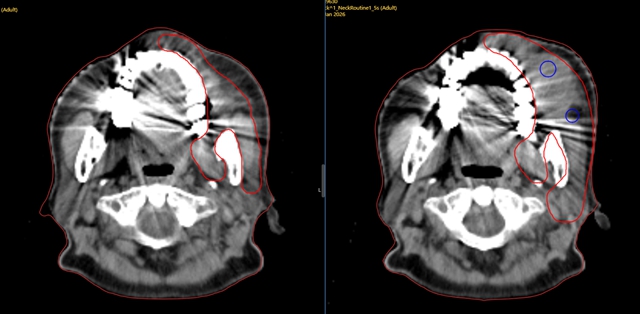

两图右上角红色圈出部分为肿瘤区域

左图为第二次放疗后,右图为第一次放疗后,通过对比可以清楚看出,经过治疗,肿瘤已明显缩小。